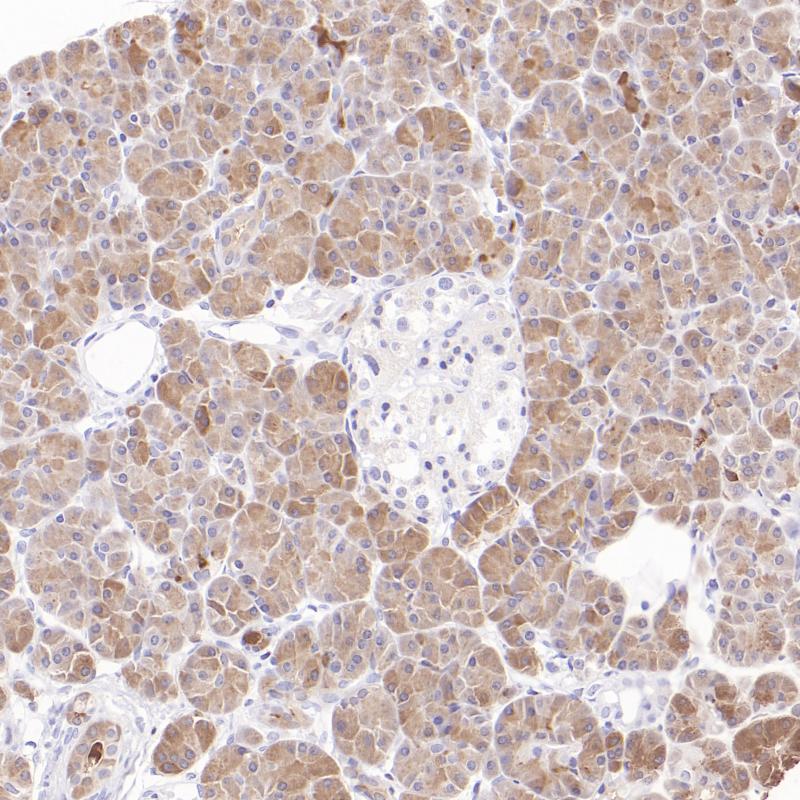

IKZF3(Ikaros锌指结构家族3,也称为Aiolos)主要通过调控靶基因的转录,参与造血干细胞分化、淋巴细胞发育及免疫稳态维持。IKZF3广泛表达于外周血白细胞、脾脏和胸腺中,其功能核心集中于B细胞的成熟、活化及抗体分泌调控,同时在T细胞、NK细胞的发育中发挥辅助作用。在肿瘤发生中,IKZF3常因基因突变、表达异常而参与细胞增殖、凋亡及耐药性的调控。IKZF3的异常表达与肿瘤风险分层相关,有助于个性化治疗计划的制定和生存结果的预测。

阳性对照

弥漫大B细胞淋巴瘤

亚细胞定位

细胞质/细胞核